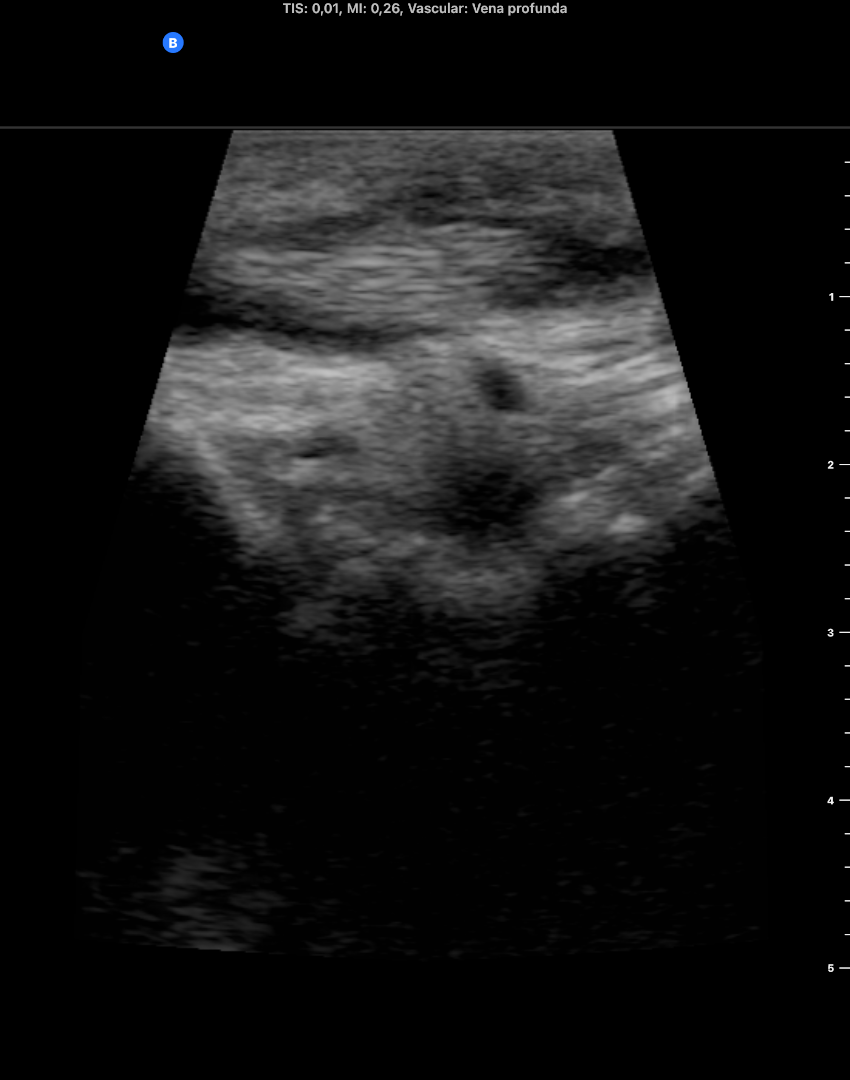

Descripción de los hallazgos ecográficos y las imágenes más relevantes para la resolución del caso

EcoscopiAP: líquido peritendinoso alrededor del tendón del m tibial anterior. Mínimo edema del tj cel sc. No TVP.